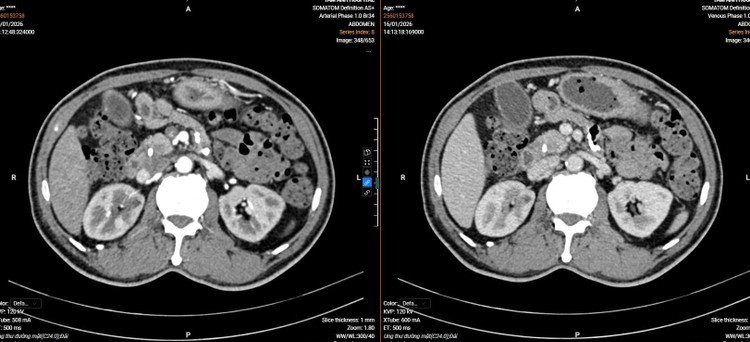

Ca phẫu thuật nội soi do các bác sĩ Bệnh viện Hữu nghị Việt Đức thực hiện - Ảnh BVCC

Theo TS.BS Nguyễn Thị Lan, Phó Trưởng khoa Phẫu thuật Gan mật, Bệnh viện Hữu nghị Việt Đức: “Phẫu thuật cắt khối tá tụy là một trong những phẫu thuật phức tạp nhất của ổ bụng, đặc biệt khi thực hiện qua nội soi, thời gian phẫu thuật khoảng 6h, đòi hỏi sự kết hợp tốt giữa các phẫu thuật viên”.

Sự phối hợp theo mô hình làm việc nhóm, phối hợp giữa các chuyên khoa, thống nhất chiến lược phù hợp với trường hợp phải điều trị đồng thời hai bệnh lý đã giúp người bệnh hồi phục nhanh, có thể đi lại sau 24 giờ.